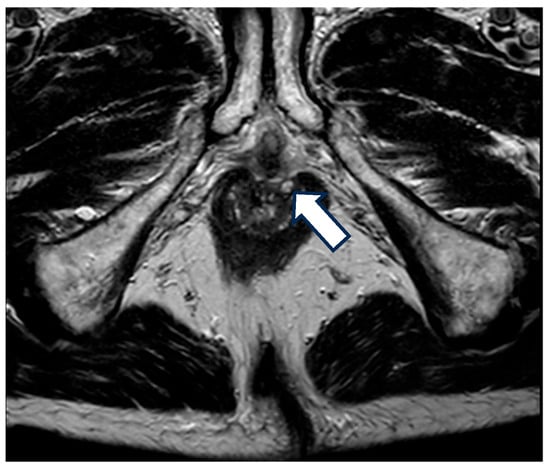

4. Classification

5. Diagnosis